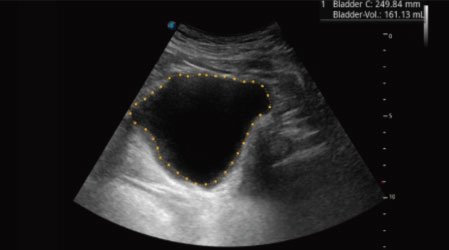

Auto Bladder

One key bladder wall tracing and volume measurement from Auto Bladder can efficiently provide more accurate contour and results, which is not subject to the bladder shape and size.